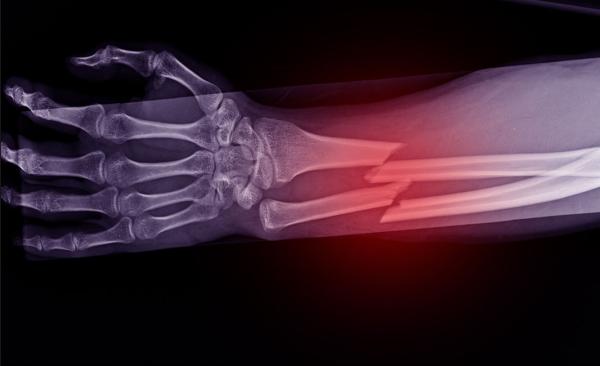

Many people have experienced a bone fracture — a partial or complete break in a bone — at some point in their lives. Fortunately, fractures eventually heal in people of any age with proper treatment, albeit more slowly in adults than in young people. However, if someone of any age ends up with a missing piece of bone much bigger than a centimeter due to a more serious trauma, that gap will never naturally fix itself. This is a particular concern when that missing piece of bone is in an area that does a lot of work, like the jaw or a leg.

Anybody can fix a fracture like this one given proper medical care and enough time, but children and teens have a unique ability to bounce back from certain forms of more extensive bone damage.